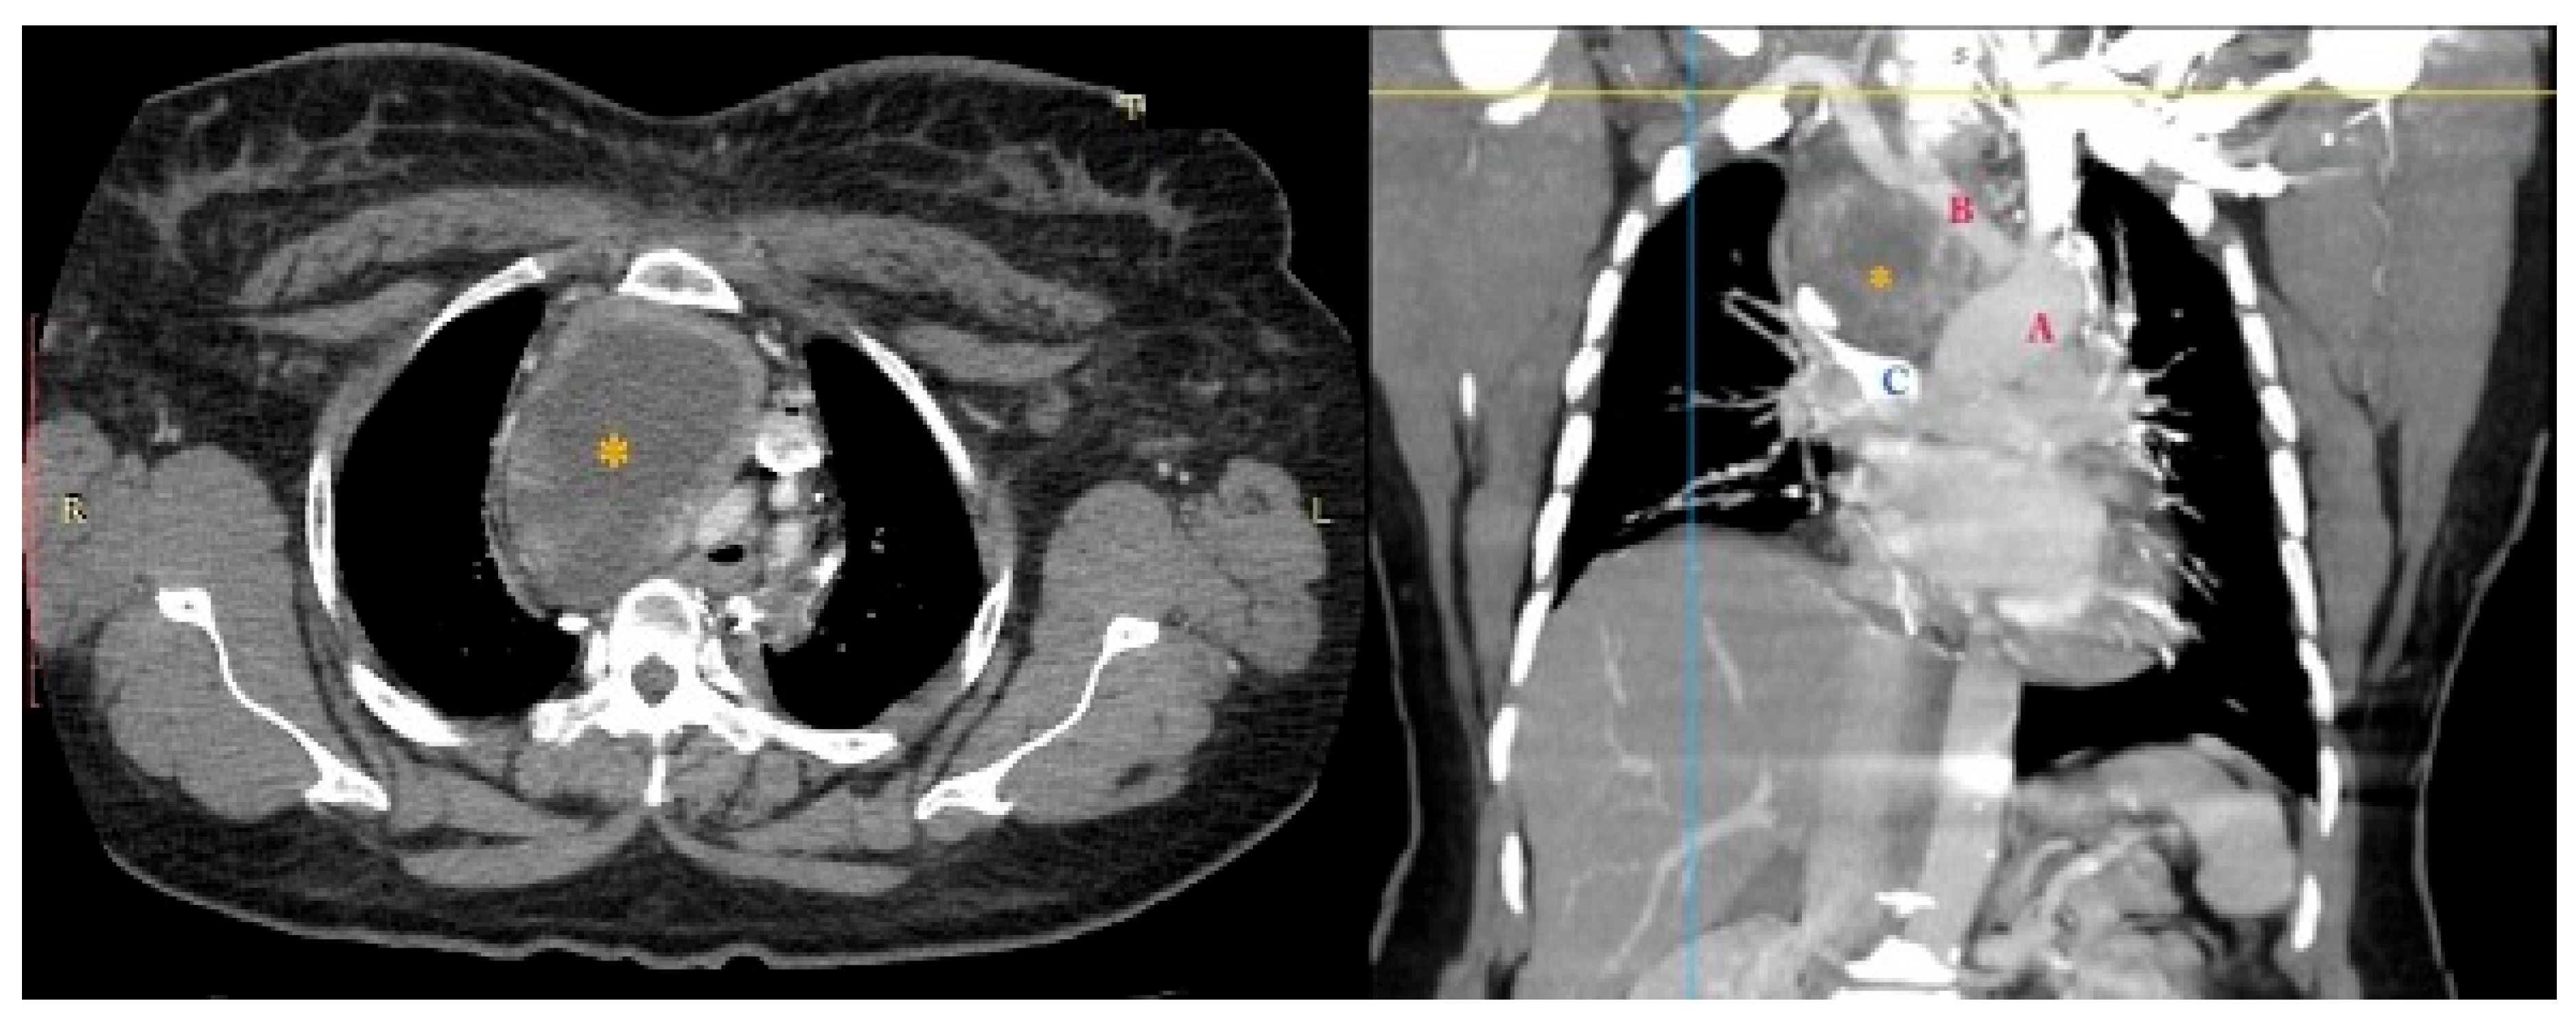

On preliminary examination, the patient was conscious with tachypnoea and tachycardia. She had puffiness with the flushing of the face, periorbital region, and neck. Oedema of both upper limbs was also noted. Jugular venous pressure was elevated, and the rest of the systemic examination was unremarkable. Preliminary blood reports were within normal limits, and a chest X-ray showed a large mass with respect to the mediastinal compartment obscuring the bilateral hila and arch of the aorta (Figure 1).

Figure 1.

Chest X-ray showing widened superior mediastinum.

The performed contrast-enhanced computerised tomography (CECT) of the chest revealed a large, well-defined, centrally necrotic, peripherally enhancing mass lesion in the superior mediastinum extending to the anterior mediastinum. There was displacement of the trachea to the left side, compression of brachiocephalic veins and proximal SVC, and a possibility of sclerotic skeletal metastasis in the vertebrae (Figure 2). A CT-guided biopsy was planned, and a fluorodeoxyglucose (FDG) positron emission tomography (PET) scan (SUV-13.1) was performed to differentiate between a malignancy or a mass with an infective lesion and to look for metastasis. The scan revealed a large 10.7 × 6.5 × 6.2 cm well-defined mass lesion of neoplastic aetiology with a mass effect—likely of thymic origin, but with no evidence of metastasis (Figure 3).

Figure 2.

CECT showing large central necrotic lesion measuring 8.4 × 6.1 × 8.2 cm involving the superior mediastinum, displacing the trachea to the left, and compressing the brachiocephalic veins and the proximal SVC. * necrotic lesion.